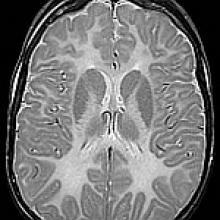

- Brain MRI showing abnormal myelin formation